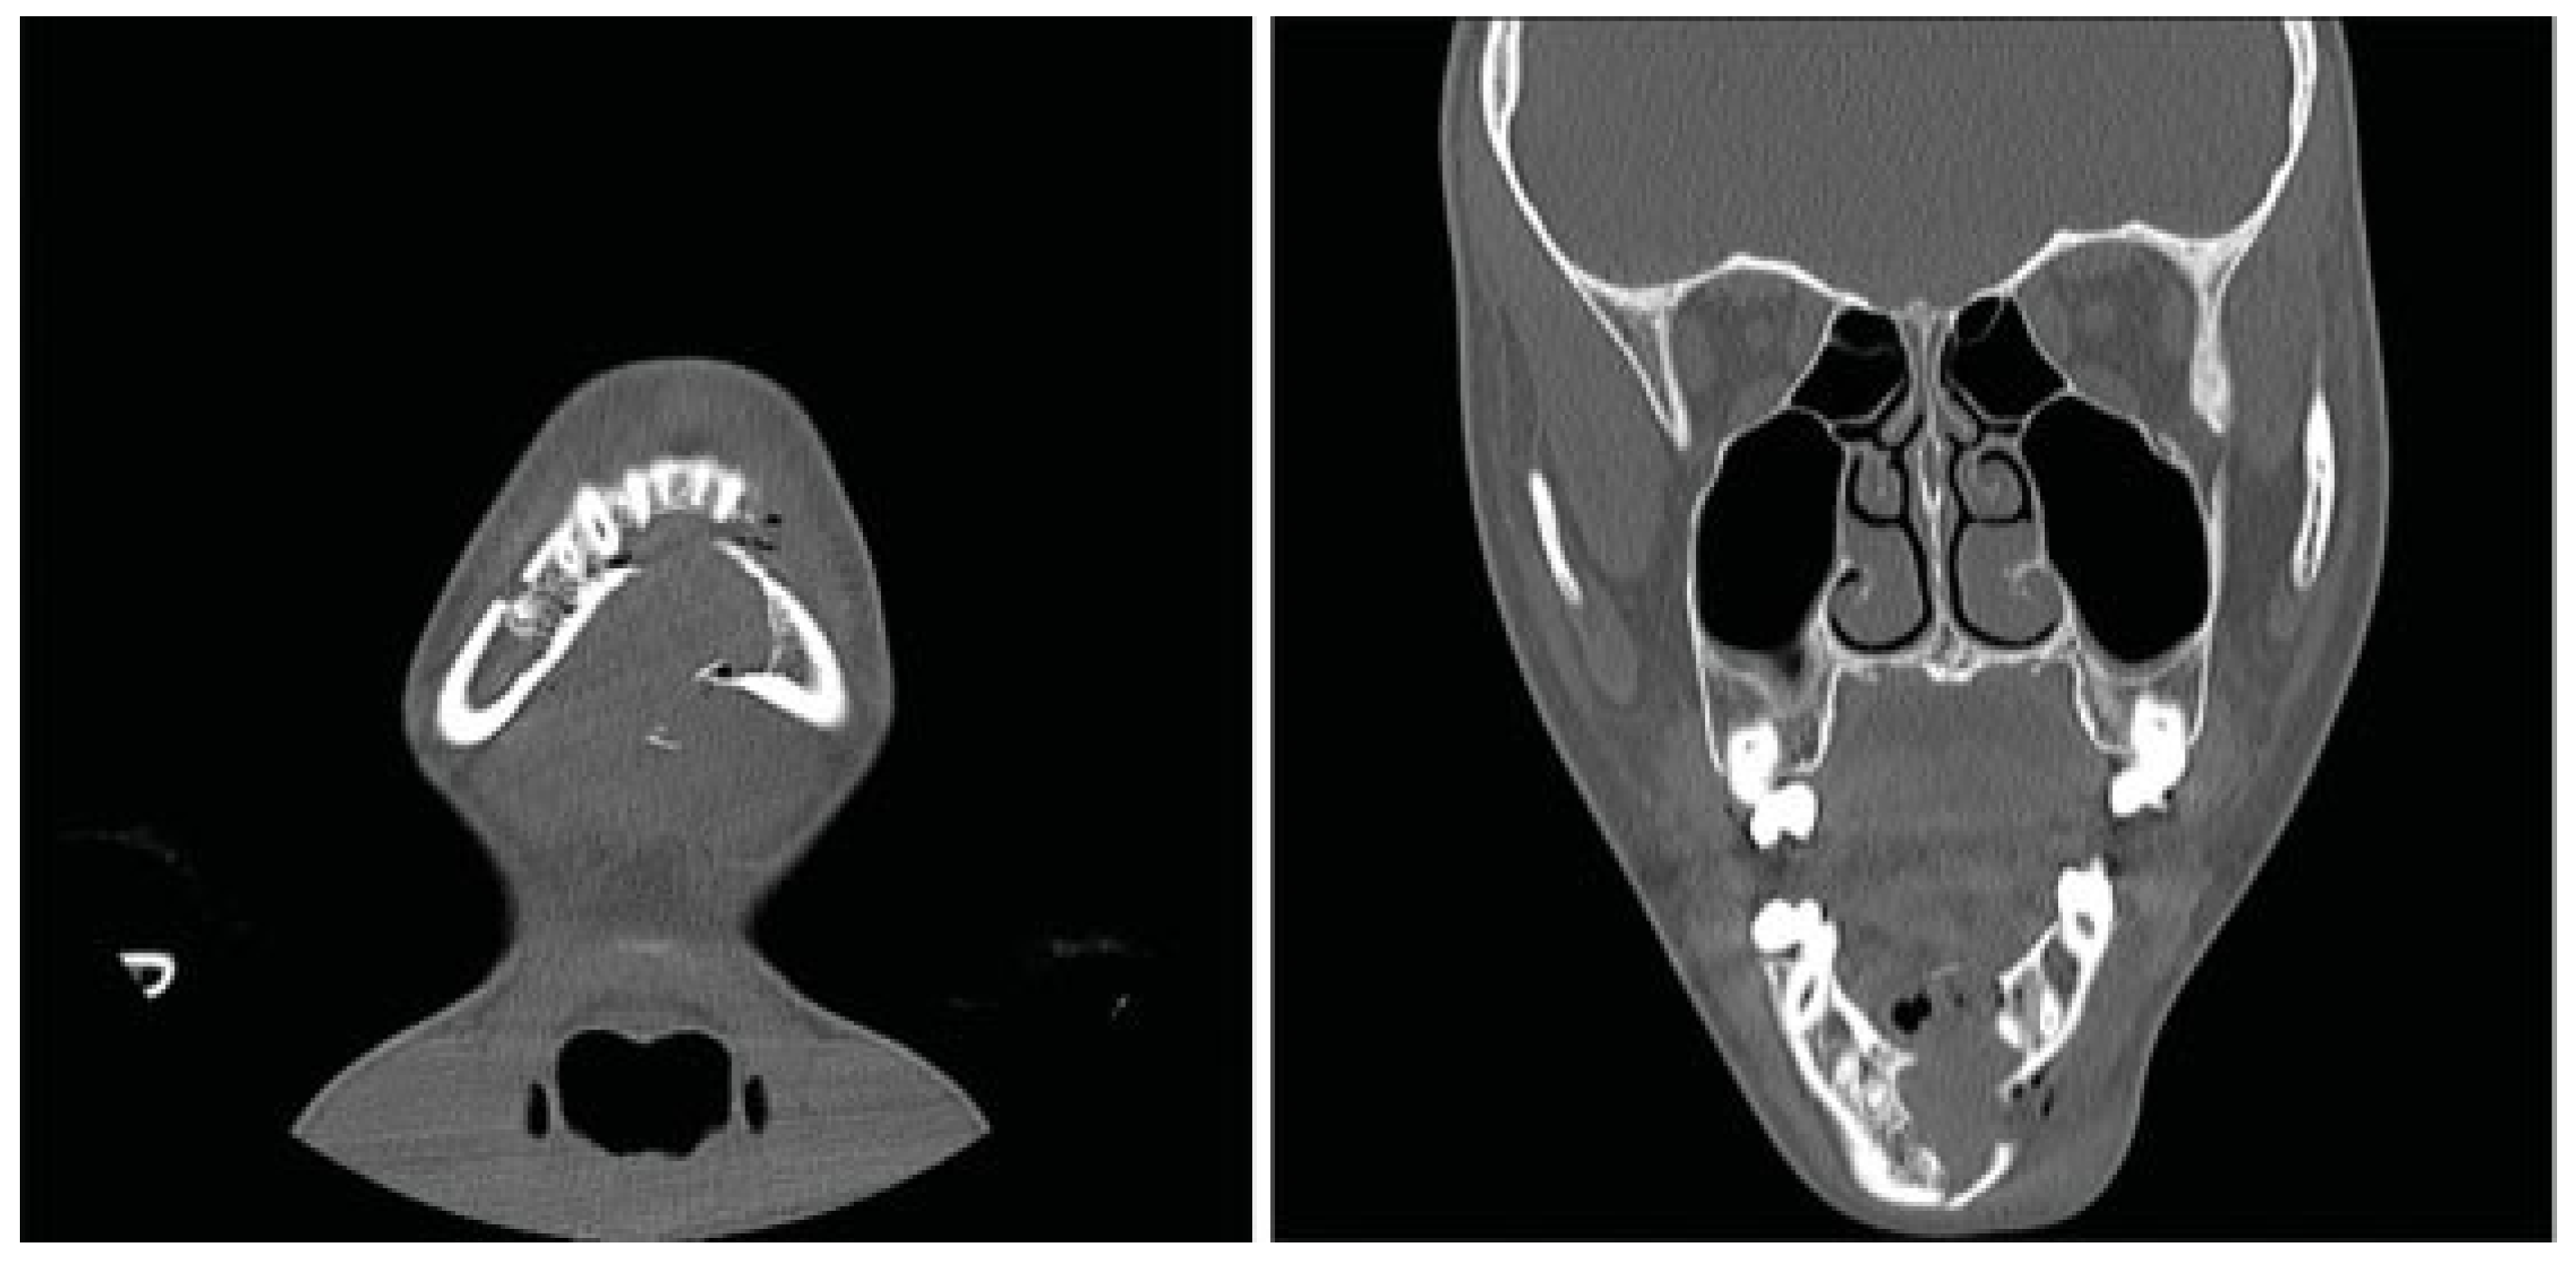

The patient was taken to the operating room the next day. With evidence of a lesion in the mandible of unknown pathology, the decision was made to proceed with a trans- cervical approach to provide broader access that would allow for adequate curettage and resection if needed. The fracture line and cystic cavity were identified. A cystic lumen was filled with organized blood clotlike material. No definitive solid tissue was identified (Figure 2). The clot and the cortex of the cavity were curetted and sent for histologic interpreta- tion. Occlusion had been established previously with max-illomandibular fixation. The mandibular fracture was reduced and repaired with a lower-border Synthes Matrix mandibular locking bar with bicortical screws (Synthes CMF, West Chester, PA, USA). An additional 2.0 Synthes Matrix mono- cortical plate was used to secure a sizable secondary fragment of the cystic wall (Figure 3). The cystic space was packed with Gelfoam (Pfizer, Pharmacia and Upjohn Company, Kalamazoo, MI, USA), as a means of filling the cystic dead space with a nonpermanent material that would not interfere with later osteogenesis. The remainder of surgery was uncomplicated and a small suction drain was placed at closing. A postoperative image revealed satisfactory alignment (Figure 4). The drain was removed on postoperative day 2, and the patient was dis-charged home 3 days later, tolerating a soft diet. Fifteen days after discharge, the patient returned to our ED with worsening pain and swelling at the surgical site. He was diagnosed with a small submental abscess. The patient was admitted and treated successfully with bedside incision and drainage and a short course of intravenous antibiotics. The remainder of his recovery was uneventful, with good occlusion and function. Follow-up CT imaging at 6 weeks showed good fracture healing and some early osteogenesis within the cystic cavity (Figure 5). One year after surgery, he had normal occlusion and no evidence of hardware complications. Additionally, CT imaging demonstrated ossification of the majority of the cystic space, with only a few small lateral areas of persistent cyst (Figure 6).

Figure 5.

Panorex computed tomography scan obtained 7 weeks postoperatively demonstrating improved anatomic alignment with some neo-osteogenesis and persistent cystic defect of the mandible.